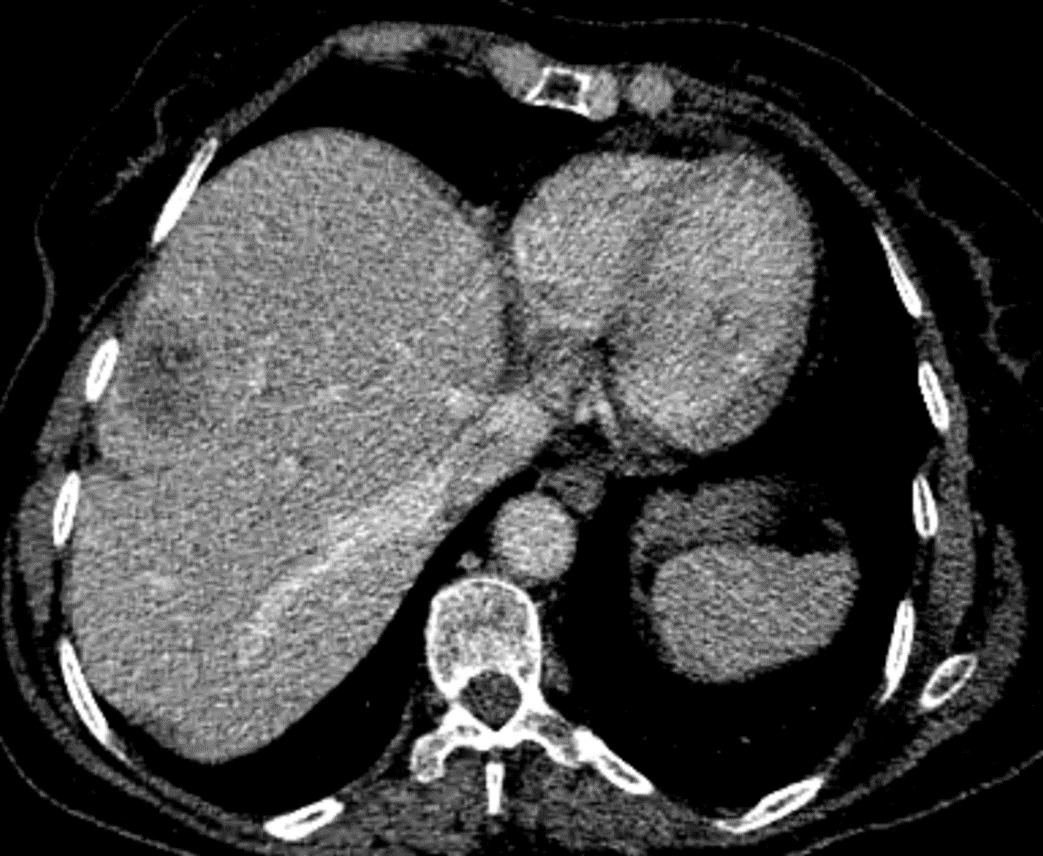

Therefore, he underwent a triple phase abdominal CT scan, revealing a poorly defined tumoral lesion in the ileocecal region, with irregular borders infiltrating the proximal colon and adjacent fat (Figure 1). The lesion showed early and intense enhancement in the arterial phase, suggesting hypervascularity. Additionally, CT-scan confirmed a well-circumscribed hypodense lesion in segment VI of the liver, which also showed early arterial enhancement (Figure 2).

Due to the nature of the enhancement, the diagnosis of a neuroendocrine colonic tumor with liver metastasis was considered. A biopsy confirmed a diagnosis of poorly differentiated neuroendocrine carcinoma of the right colon. Given the high histological grade, the patient’s general condition, and the presence of hepatic metastasis, primary surgical management was not considered appropriate, and chemotherapy was proposed. Unfortunately, the patient passed away before starting treatment.

Contrast-enhanced CT and MRI are among the most commonly used modalities.6 CT is typically the first-line investigation for suspected neuroendocrine tumors, useful for staging and surgical planning.7 Primary gastrointestinal lesion as well as their metastases typically appear hyperenhancing with intravenous contrast, best seen in the arterial phase of a triple-phase CT.7